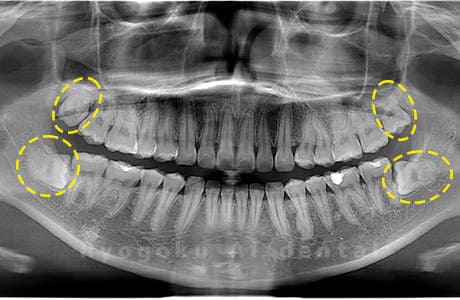

真っ直ぐ生えている親知らず

親知らずが真っ直ぐ生えているタイプです。

このタイプは真っ直ぐ生えていて咬み合わせに問題がなければ、抜歯しないケースもあります。ただし、虫歯になっていたり、痛みがあったり、咬み合わせが悪かったりすると抜歯をおすすめします。